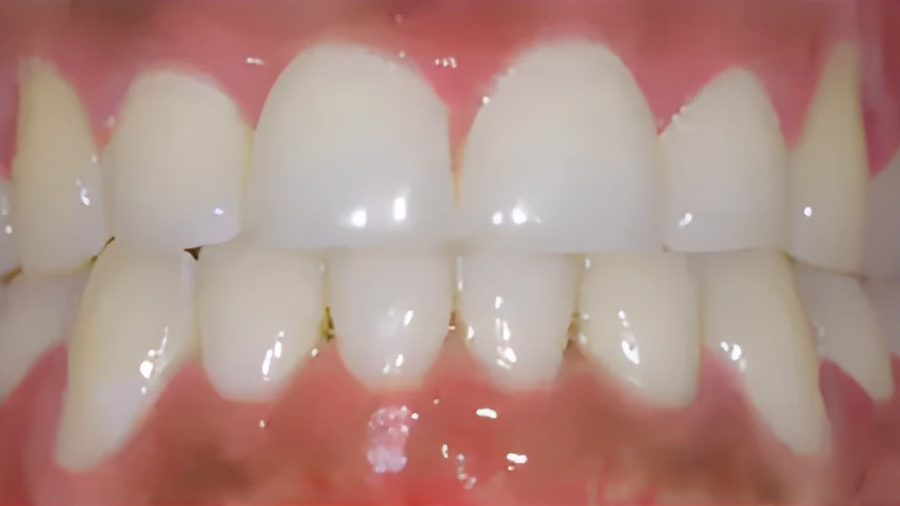

This patient had severe upper and lower crowding that was corrected to a straight and balanced smile.

These photos are actual patients of Rafati Orthodontics. Results may vary in individual cases.